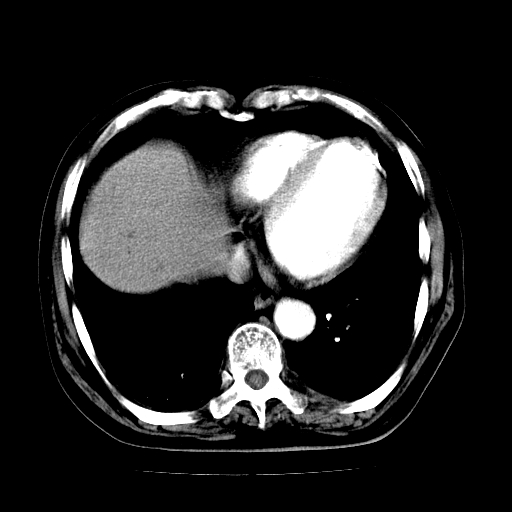

男,71岁,皮肤黄染四天。

肝内外胆管及胆总管上段扩张,考虑为梗阻所致,建议mrcp检查。

考虑胆总管癌并肝内外胆管扩张。

胰腺上端胆总管内见软组织影,强化不明显,结合临床,还是考虑低位梗阻性黄疸,胆总管癌可能性大